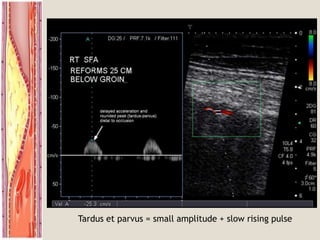

 normal is triphasic  biphasic  monophasic  absent

Tardus et parvus = small amplitude + slow rising pulse

Tardus et parvus= small amplitude + slow rising pulse